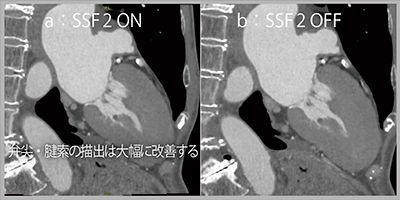

症例2は肥大型心筋症を伴う僧帽弁閉鎖不全症に対しMitraClip治療を行った症例である。SnapShot Freeze 2を適用したCT画像では,経食道心エコーで不明瞭であった後尖の接合部付近のCFZが確認できた。また,SnapShot Freeze 2の適用の有無を比較すると(図2),適用なしの画像(b)では弁尖が消失しているが,適用ありの画像(a)では弁尖の全体像や腱索も明瞭に描出されている。

SnapShot Freeze2を用いることで,MitraClip治療においてクリップの留置位置を自信を持って決定できるなど,治療戦略の構築に寄与する。

図2 症例2:僧帽弁閉鎖不全症